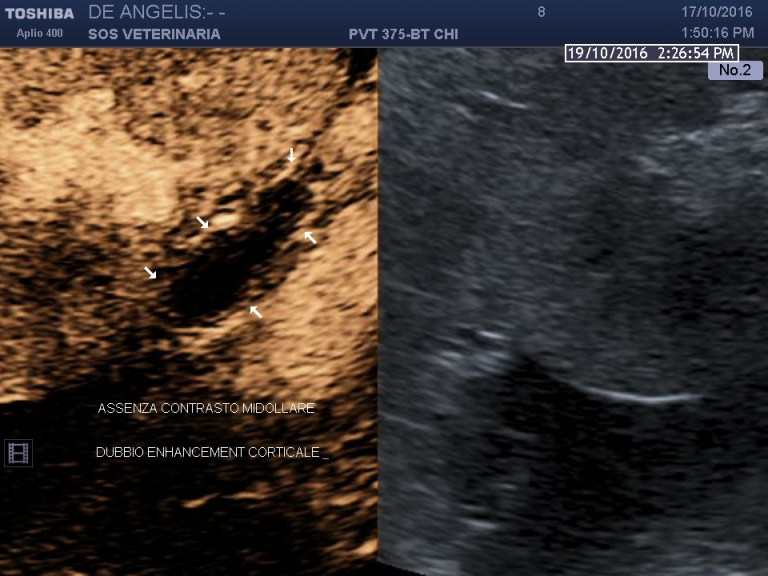

esame ecografico ceus

evidente assenza di enhancementin tutte le fasi forse un debole presa di contrasto sottocapsulare in periferia

la registrazione per errore e’ partita dopo alcuni secondi e non si visualizza l arrivo del contrasto , la ghiandola e’ rimastapriva di enhancementin tutte le fasi anche dopo il flash che rompe le bolle si puo’ notare la completa assenza di riperfusione